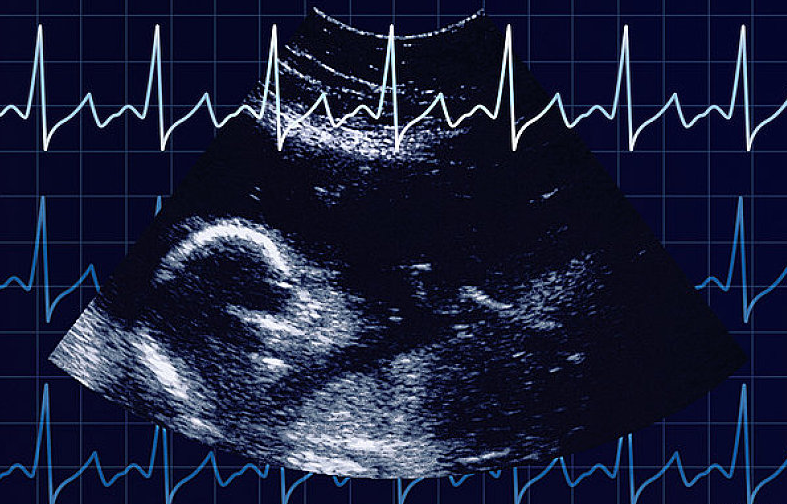

通過(guò)胎心監(jiān)護(hù)能了解到胎兒在子宮內(nèi)的情況,因此,孕媽們應(yīng)按時(shí)產(chǎn)檢,從孕32周(患有妊娠高血壓等疾病的孕媽從孕28周)開(kāi)始就要進(jìn)行胎心監(jiān)護(hù)。

當(dāng)各種原因引起胎兒缺氧時(shí),胎心很敏感地會(huì)出現(xiàn)變化。胎兒正常的胎心率為110~160次/分,正常的胎兒心率隨子宮內(nèi)環(huán)境的不同,時(shí)刻發(fā)生著變化,胎心率的變化是中樞神經(jīng)系統(tǒng)正常調(diào)節(jié)機(jī)能的表現(xiàn),也是胎兒在子宮內(nèi)狀態(tài)良好的表現(xiàn)。若胎心率分或>160次/分,持續(xù)10分鐘以上,稱為胎心過(guò)緩或胎心過(guò)速。